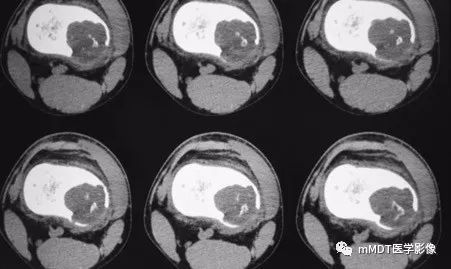

病史:15岁男性,右膝不适2年,行走及上楼时疼痛不明显。查体:右膝内侧膨隆,屈曲略受限,局部皮温正常,皮肤完整。影像资料如下:

CT横断面软组织窗

CT见病变位于股骨远端干骺端,呈分叶状、偏心膨胀性生长,密度欠均匀,整体低于肌肉密度,部分区域密度接近水,其内可见点状、线状、弧形、圆形的高密度影,大部分边缘硬化,局部深侵蚀骨内膜,局部骨壳不完整。MR上,T1WI信号略低于肌肉,T2压脂呈现不均匀高信号,未见明确软骨小叶结构及纤维分隔,周围可见水肿。